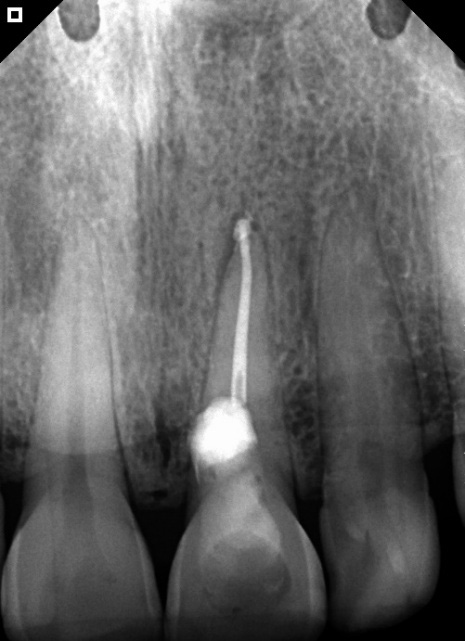

At the school clinic, access to the tooth was tried again, but due to the anatomical conditions of this tooth, perforation occurred (Figure 2). After controlling the bleeding in the region, the canal was accessed. Calcium hydroxide was placed as a temporary dressing.

Figure 2: Perforation